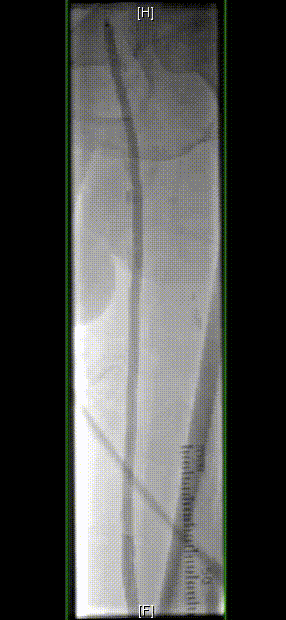

图为:术中造影评估 膝下踝下段

图为:导丝通过病变 置入保护伞 使用Turbohawk定向旋切

图为:血管准备:股浅旋切后球囊全程节段逐级式扩张